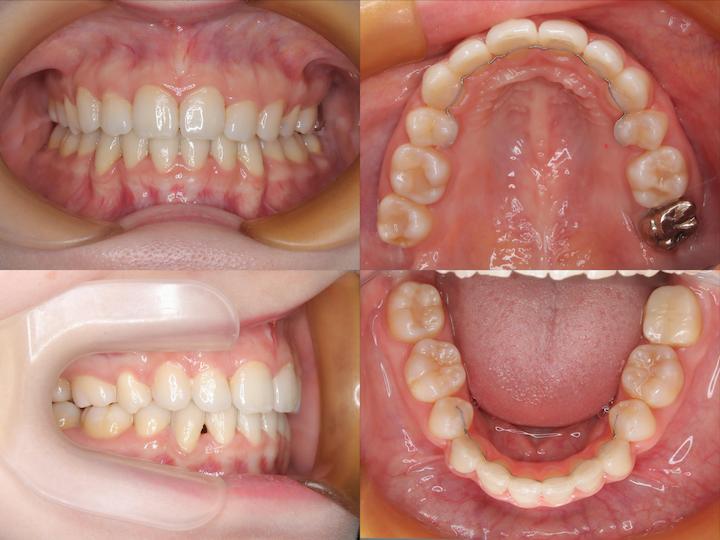

治療期間:2年11ヶ月

初診時年齢33歳5ヶ月の患者様です。口の閉じ辛さと歯の重なりを主訴にご来院されました。

上下左右4番を抜歯してアンカースクリューで上顎6番を遠心移動しながら前歯を後方に牽引しました。

さらに上顎大臼歯を圧下(上方向に移動)して下顎骨の前上方への回転を促しました。

本症例は前歯の移動量が大きいことから上顎前歯が切歯孔にぶつかるリスクがあります。初診時とアンカースクリュー埋入時のCTデータから歯根の位置を確認しながら上顎前歯の後方移動を行いました。